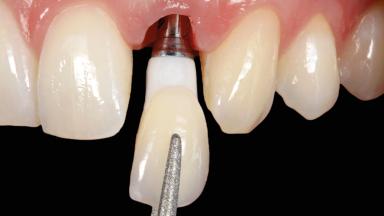

Immediate Implant Placement and Immediate Provisionalization with a Prefabricated-Shell Provisional Crown

In this case, Arndt Happe describes how he achieved a stable outcome at 5 years by giving careful attention to the coronal aspect of the transmucosal area of the provisional, creating a slim emergence profile.